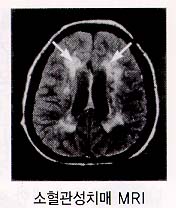

2. Ç÷°ü¼ºÄ¡¸Å

Ç÷°ü¼º Ä¡¸Å¶õ ³úÇ÷°üÁúȯ¿¡ ÀÇÇÑ ³ú¼Õ»óÀÌ ´©ÀûµÇ¾î ³ªÅ¸³ª´Â Ä¡¸Å¸¦ ¸»ÇÕ´Ï´Ù. À§ÇèÀÎÀڷδ °íÇ÷¾Ð, ´ç´¢º´, °íÁöÇ÷Áõ, ½ÉÀ庴, Èí¿¬, ºñ¸¸À» °¡Áø »ç¶÷¿¡°Ô¼

¸¹ÀÌ ³ªÅ¸³³´Ï´Ù. ±× Áß¿¡¼µµ °íÇ÷¾ÐÀÌ °¡Àå ¹«¼¿î À§Çè¿ä¼ÒÀÔ´Ï´Ù.

Á¤»óÀûÀÎ Ç÷°üº®Àº ¸»¶û¸»¶ûÇϰí Åõ¸íÇѵ¥ °íÇ÷¾ÐÀÌ ¿À·¡ Áö¼ÓµÇ¸é Ç÷°üº®ÀÇ ±ÙÀ°ÃþÀÌ µÎ²¨¿öÁý´Ï´Ù. ÀÌ·¯ÇÑ ±ÙÀ°ÃþÀº Ç÷°ü ¾ÈÂÊÀ¸·Î ¹ß´ÞÇÏ°Ô µÇ±â ¶§¹®¿¡ °á±¹Ç÷°üÀÌ Á¼¾ÆÁö°Ô µË´Ï´Ù. Å« Ç÷°üÀÌ ¸·È÷°Å³ª ÅÍÁö¸é ¹Ý½ÅºÒ¼ö, ¾ð¾îÀå¾Ö µî ±Ý¹æ ´«¿¡ º¸ÀÌ´Â Àå¾Ö°¡ ³ªÅ¸³ª°í, ÀÌ·± ³ú°æ»öÀÌ ¹Ýº¹µÉ °æ¿ì ´Ù¹ß¼º ³ú°æ»ö¼º Ä¡¸Å°¡ ¹ß»ýÇÏ°Ô µË´Ï´Ù. ÀÌ¿¡ ¹ÝÇØ ÀÛÀº Ç÷°üÀÌ ¼Õ»óµÇ¸é ±× ¼Õ»óµÇ´Â ³ú¼¼Æ÷ÀÇ ¾çÀÌ ¸Å¿ì ¼Ò·®À̱⠶§¹®ÀÌ ´«¿¡ ¶çÁö ¾Ê°Ô µÇ°í ÀÌ·± º¯È°¡ ´©ÀûµÇ¾î °á±¹ ¼ÒÇ÷°ü¼º Ä¡¸Å¿¡ À̸£°Ô µË´Ï´Ù.

ƯÈ÷ ¿À·§µ¿¾È °íÇ÷¾ÐÀ̳ª ´ç´¢º´ µîÀ¸·Î °í»ýÇϼ̴ø ºÐµé Áß¿¡¼ ¾ðÁ¦ºÎÅÏÁö ¸ð¸£°Ô ¼¼È÷ »ý°¢Çϰí ÇൿÇÏ´Â °ÍÀÌ ÀÌ»óÇØÁ³´Ù°í º¸È£ÀںеéÀÌ ¸ð½Ã°í ¿À´Â °æ¿ì°¡ ÀÖ½À´Ï´Ù. ÁøÂûÇØ º¸¸é »ó¼úÇÑ ¿©·¯ ¼Ò°ßµéÀÌ °üÂûµÇ¾î Ç÷°ü¼º Ä¡¸Å¸¦ ÀǽÉÇÏ°í °¢Á¾ °Ë»ç¸¦ ½ÃÇà ÈÄ È®Áø¿¡ À̸£°Ô µË´Ï´Ù. ¾ÈŸ±î¿î °ÍÀº ÀÌ·¯ÇÑ ºÐµé Áß´ë´Ù¼ö¿¡¼ °ú°Å¿¡ °æ¹ÌÇÏ°Ô ³úÁ¹ÁßÀÌ ¿Ô´ø ÀÏÀÌ ÀÖ¾úÀ½¿¡µµ º°´Ù¸¥ ³úÁ¹Áß¿¡ ´ëÇÑ ¿¹¹æÃ¥À» ÃëÇÏÁö ¾Ê¾Ò´Ù´Â Á¡ÀÔ´Ï´Ù. ¸¸¾à Á¶±â¿¡ Áø´ÜÇÒ ¼ö ÀÖ¾ú´Ù¸é ´õ ÀÌ»óÀÇ ÁøÇàÀ» ¸·À» ¼öµµ ÀÖ°í ½ÉÁö¾î´Â È£ÀüµÇ¾î °ÅÀÇ Á¤»óÈ µÇ±âµµ ÇÏ´Â °ÍÀÌ ³úÇ÷°üÁúȯÀ̰í ÀÌ·Î ÀÎÇØ ¹ß»ýÇÏ´Â Ç÷°ü¼º Ä¡¸Å ¿ª½Ã ±×·¯ÇÕ´Ï´Ù. Á¶±âÁø´Ü°ú Ä¡·áÀÇ Á߿伺Àº ƯÈ÷ ¼±¸¿Í´Â ´Þ¸® ¿ì¸®³ª¶óÀÇ °æ¿ì Ç÷°ü¼º Ä¡¸Å°¡ Ä¡¸ÅÀÇ »ó´çÇÑ ºÎºÐÀ» Â÷ÁöÇϰí ÀÖ´Ù´Â Á¡¿¡¼ ´õ¿í °Á¶ÇÏÁö ¾ÊÀ» ¼ö ¾ø½À´Ï´Ù.

Áø´Ü

¾ËÂêÇÏÀ̸Ӻ´°ú ¸¶Âù°¡Áö·Î Ä¡¸Å¿¡ ¼÷·ÃµÈ Àǻ簡 ÁøÂû°ú ¿©·¯ °Ë»ç °úÁ¤À» ÅëÇÏ¿© Ç÷°ü¼ºÄ¡¸ÅÀÎÁö ¾Æ´Ï¸é ´Ù¸¥ ¿øÀο¡ ÀÇÇÑ Ä¡¸ÅÀÎÁö¸¦ È®ÀÎÇÏ°Ô µË´Ï´Ù. °Ë»ç¿¡´Â Ç÷¾×°Ë»ç, ´¢°Ë»ç, ÈäºÎ¹æ»ç¼±°Ë»ç, ½ÉÀüµµ ³úÆÄ°Ë»ç ¹× ÀÚ±â°ø¸í°Ë»ç(MRI) µîÀÌ ÀÖ½À´Ï´Ù. Ä¡¸Å Áõ»óÀÌ ÀÖÀ¸¸é¼ ½Å°æÇÐÀû °Ë»ç»ó ÀÌ»ó¼Ò°ßÀÌ ÀÖ°í ³ú ÃÔ¿µ»ó ±× ÀÌ»ó¼Ò°ßÀ» µÞ¹ÞħÇÒ ¼ö ÀÖ´Â ¼Ò°ßÀÌ º¸À̸é È®ÁøÇÒ ¼ö ÀÖ½À´Ï´Ù. »ó±â ¿°ÅÇÑ Ç÷°ü¼º Ä¡¸ÅÀÇ À§Çè¿ä¼Ò, ƯÈ÷ °íÇ÷¾Ð ȯÀÚ¿¡¼ ½Å°æÇÐÀû ÀÌ»ó¼Ò°ßÀÌ ÀÖ°í ±â¾ïÀå¾Ö µî »ç°í·ÂÀÇ ÀúÇϰ¡ ÀÇ½ÉµÉ ¶§´Â ÀÏ´Ü Ç÷°ü¼º Ä¡¸ÅÀÇ °¡´É¼ºÀ» »ý°¢Çϰí Ä¡¸Å Àü¹®º´¿øÀ» ¹æ¹®Çϰųª ³ú ÀÚ±â°ø¸í¿µ»óÃÔ¿µÀ» ½Ç½ÃÇÏ¿©¾ß ÇÕ´Ï´Ù.